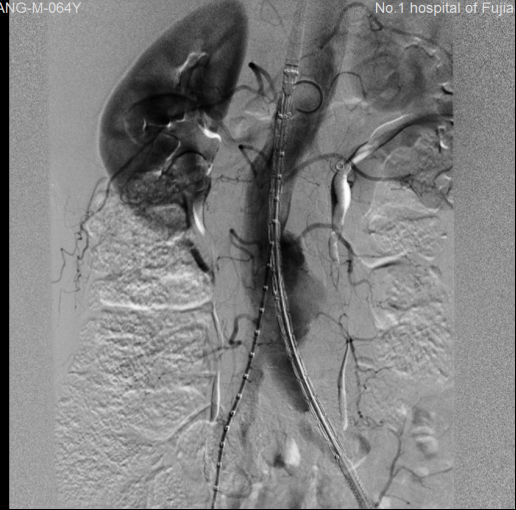

术前 术后